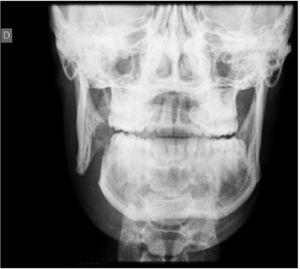

Se sol·licità radiografia simple (fig. 1), que mostrà fractura completa de la branca mandibular dreta i fractura lineal parasimfisària esquerra. Com que no es disposava d’ortopantomografia d’urgència se sol·licità tomografia computeritzada mandibular, que evidencià fractura desplaçada de l’angle mandibular dret amb emfisema subcutani (fig. 2) i fractura parasimfisària esquerra no desplaçada.

Figura 1. Fractura completa de branca mandibular dreta i fractura lineal parasimfisària esquerra d’un jugador d’hoquei herba de 17 anys amb contusió facial directa.

Per al diagnòstic de les fractures mandibulars, la radiografia panoràmica o ortopantomografia proporciona una primera visió general molt acceptable, però en molts serveis d’urgències aquesta prova no està disponible. En aquesta situació la radiologia simple amb projecció AP (fig. 1) de Towne i obliqua lateral dreta i esquerra generalment permet visualitzar la fractura, però en cas de radiografia aparentment normal i sospita diagnòstica alta, cal sollicitar una tomografia computeritzada mandibular (fig. 2). La tomografia computeritzada és l’estudi òptim per visualitzar la mandíbula en tots els plans i, sobretot, els còndils, que freqüentment s’han desplaçat per la tracció de la musculatura masticatòria i es troben fora del pla, per la qual cosa a vegades les fractures a aquest nivell passen desapercebudes amb proves radiològiques convencionals.